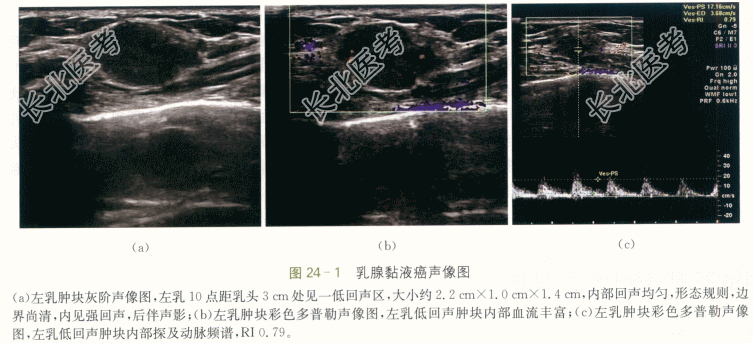

左乳黏液癌(中等分化)。